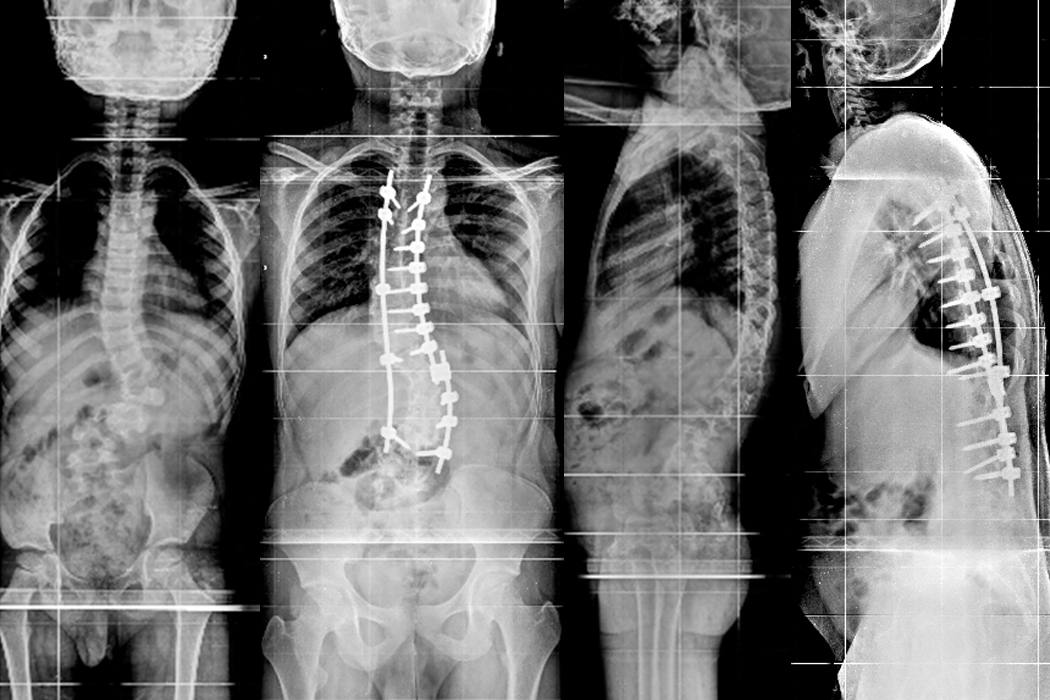

Patient A

In the year 2017 a 12 year old school girl presented with severe deformity over the back noticed 3 years ago. She underwent Anterior and Posterior Scoliosis correction.

Hover over the image to view Pre & Post-op X-Rays